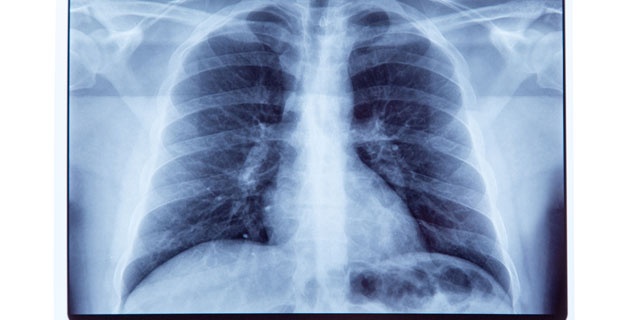

マイコプラズマ肺炎とは

マイコプラズマに感染することによって起こる肺炎であり、マイコプラズマは感染すると気管支炎から肺炎やぜんそくなどを起こします。

潜伏期間は2~3週間程度とされ、過去には子供に多いとされていましたが、近年は大人でも罹患される方が増えています。マイコプラズマによる肺炎は、肺炎全体の5%を占めるといわれています。